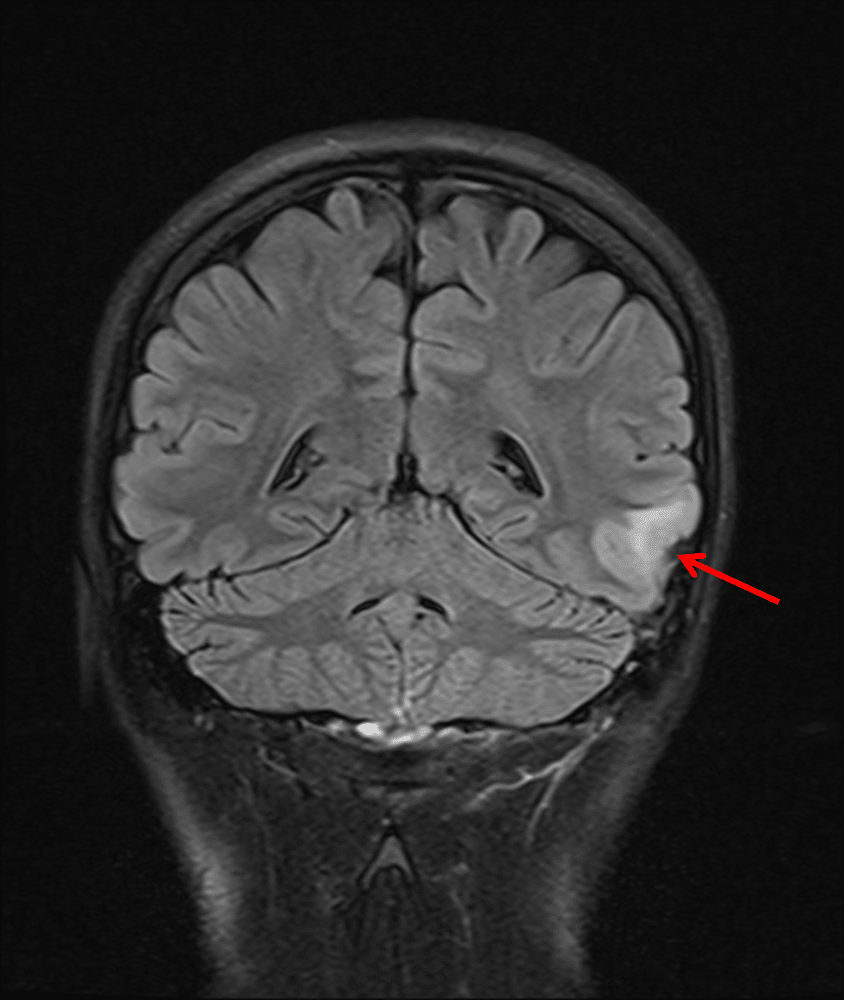

Small area of FLAIR signal hyperintensity in the left middle temporal gyrus (red arrow).